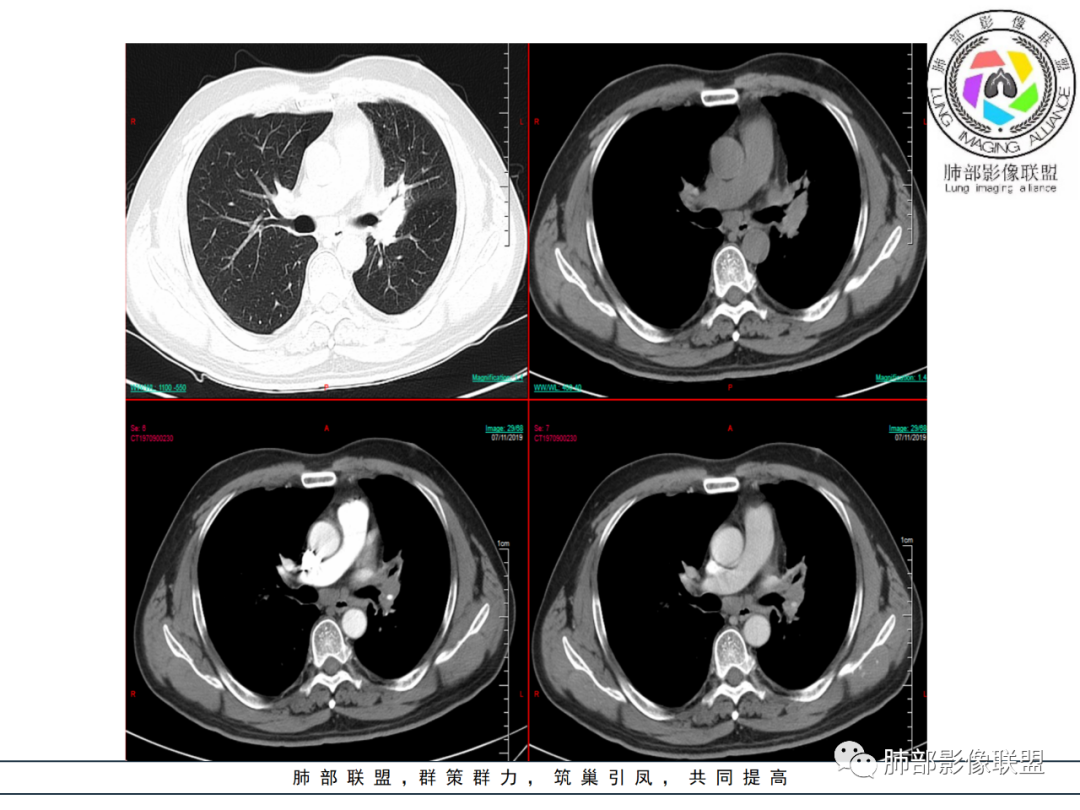

中年男性,左肺肺门区占位伴肺不张,上叶尖段气管外压性狭窄,增强病灶未见明显坏死。首先定性还是恶性,病灶未见明显坏死,周围毛刺分叶都有,首先考虑腺癌可能性大。

老年男性,细胞角质蛋白19片段指标偏高,左肺门软组织密度影,左肺上叶支气管开口狭窄,增强可见肺动脉受压,纵隔内见肿大淋巴结影,考虑鳞癌

左肺上叶体积缩小,透光度减低,局部肺不张,左肺门肿块,左肺上叶支气管被包绕呈鼠尾状狭窄,左肺主动脉被包绕受侵犯,纵隔内多发肿大淋巴结,左肩胛骨周围软组织内多发针状钙化,首先定恶性,考虑1小细胞肺癌2腺癌

中年男性 左肺门软组织肿块,包绕支气管呈鼠尾状狭窄,远端少许阻塞性改变,增强扫描肺门血管受压变性,肿块均匀强化,未见明显强化,肿块向肺门纵隔延伸,肺门纵隔脂肪分界不清。诊断,恶性占位,男性肺门肿块鳞癌需要考虑,但是没有湖泊坏死,没有明显阻塞性改变;小细胞,纵隔淋巴结没有明显融合,但是肺门侧有融合冰冻表现,不能排除。另外病灶边缘分叶、毛刺形成,强化均匀,猜一个腺鳞癌不除外。最后诊断 小细胞或腺鳞癌

晕晕菜:

患者中年男性,咳嗽、咳痰1月余,同时伴有胸闷不适。胸CT:左肺上叶占位并膨胀不全,左肺上叶支气管支气管不规则狭窄,左肺固有上叶开口呈鼠尾状闭塞。纵隔窗:4L 4R 6 7 左肺门淋巴结肿大,增强静脉期较动脉期强化,血管包埋,左肺下叶肺动脉纤细。 医学百科网 | YxBaike.Com

考虑: 医学百科网 | YxBaike.Com

1:恶性病变—–小细胞肺癌 医学百科网 | YxBaike.Com

2:良性病变—–结核 医学百科网 | YxBaike.Com

建议支气管镜检查。